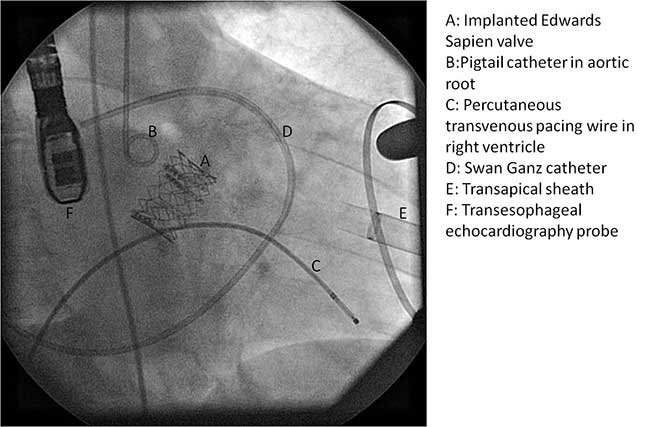

Once the positioning of the valve is confirmed by echocardiography and fluoroscopy, balloon valvuloplasty is performed in a similar fashion to the transfemoral approach described earlier. Upon restoring stable hemodynamics, the mounted Sapien valve on a balloon catheter is introduced transapically and proper position is confirmed by echocardiography and angiography (Figure 4C). For the transapical approach, the recommended position of the prosthesis is 50% of the prosthesis on the aortic side of the aortic annulus and 50% on the ventricular side of the annulus. Since the delivery system is much shorter compared to the transfemoral approach, the direct apical access to the aortic annulus results in less stored torque in the system. Therefore on deployment, the prosthesis does not have the tendency to migrate. During a period of rapid ventricular pacing, the valve is rapidly deployed by expanding the balloon (Figure 5). The valve is not re-ballooned unless there is moderate to severe paravalvular leak. The ventricular sheath is then removed and hemostasis is achieved by tying down the apical purse string sutures during rapid ventricular pacing. Great care must be taken in tying these sutures, as too much tension or torque may cause the ventricular apex to tear and cause uncontrollable bleeding.